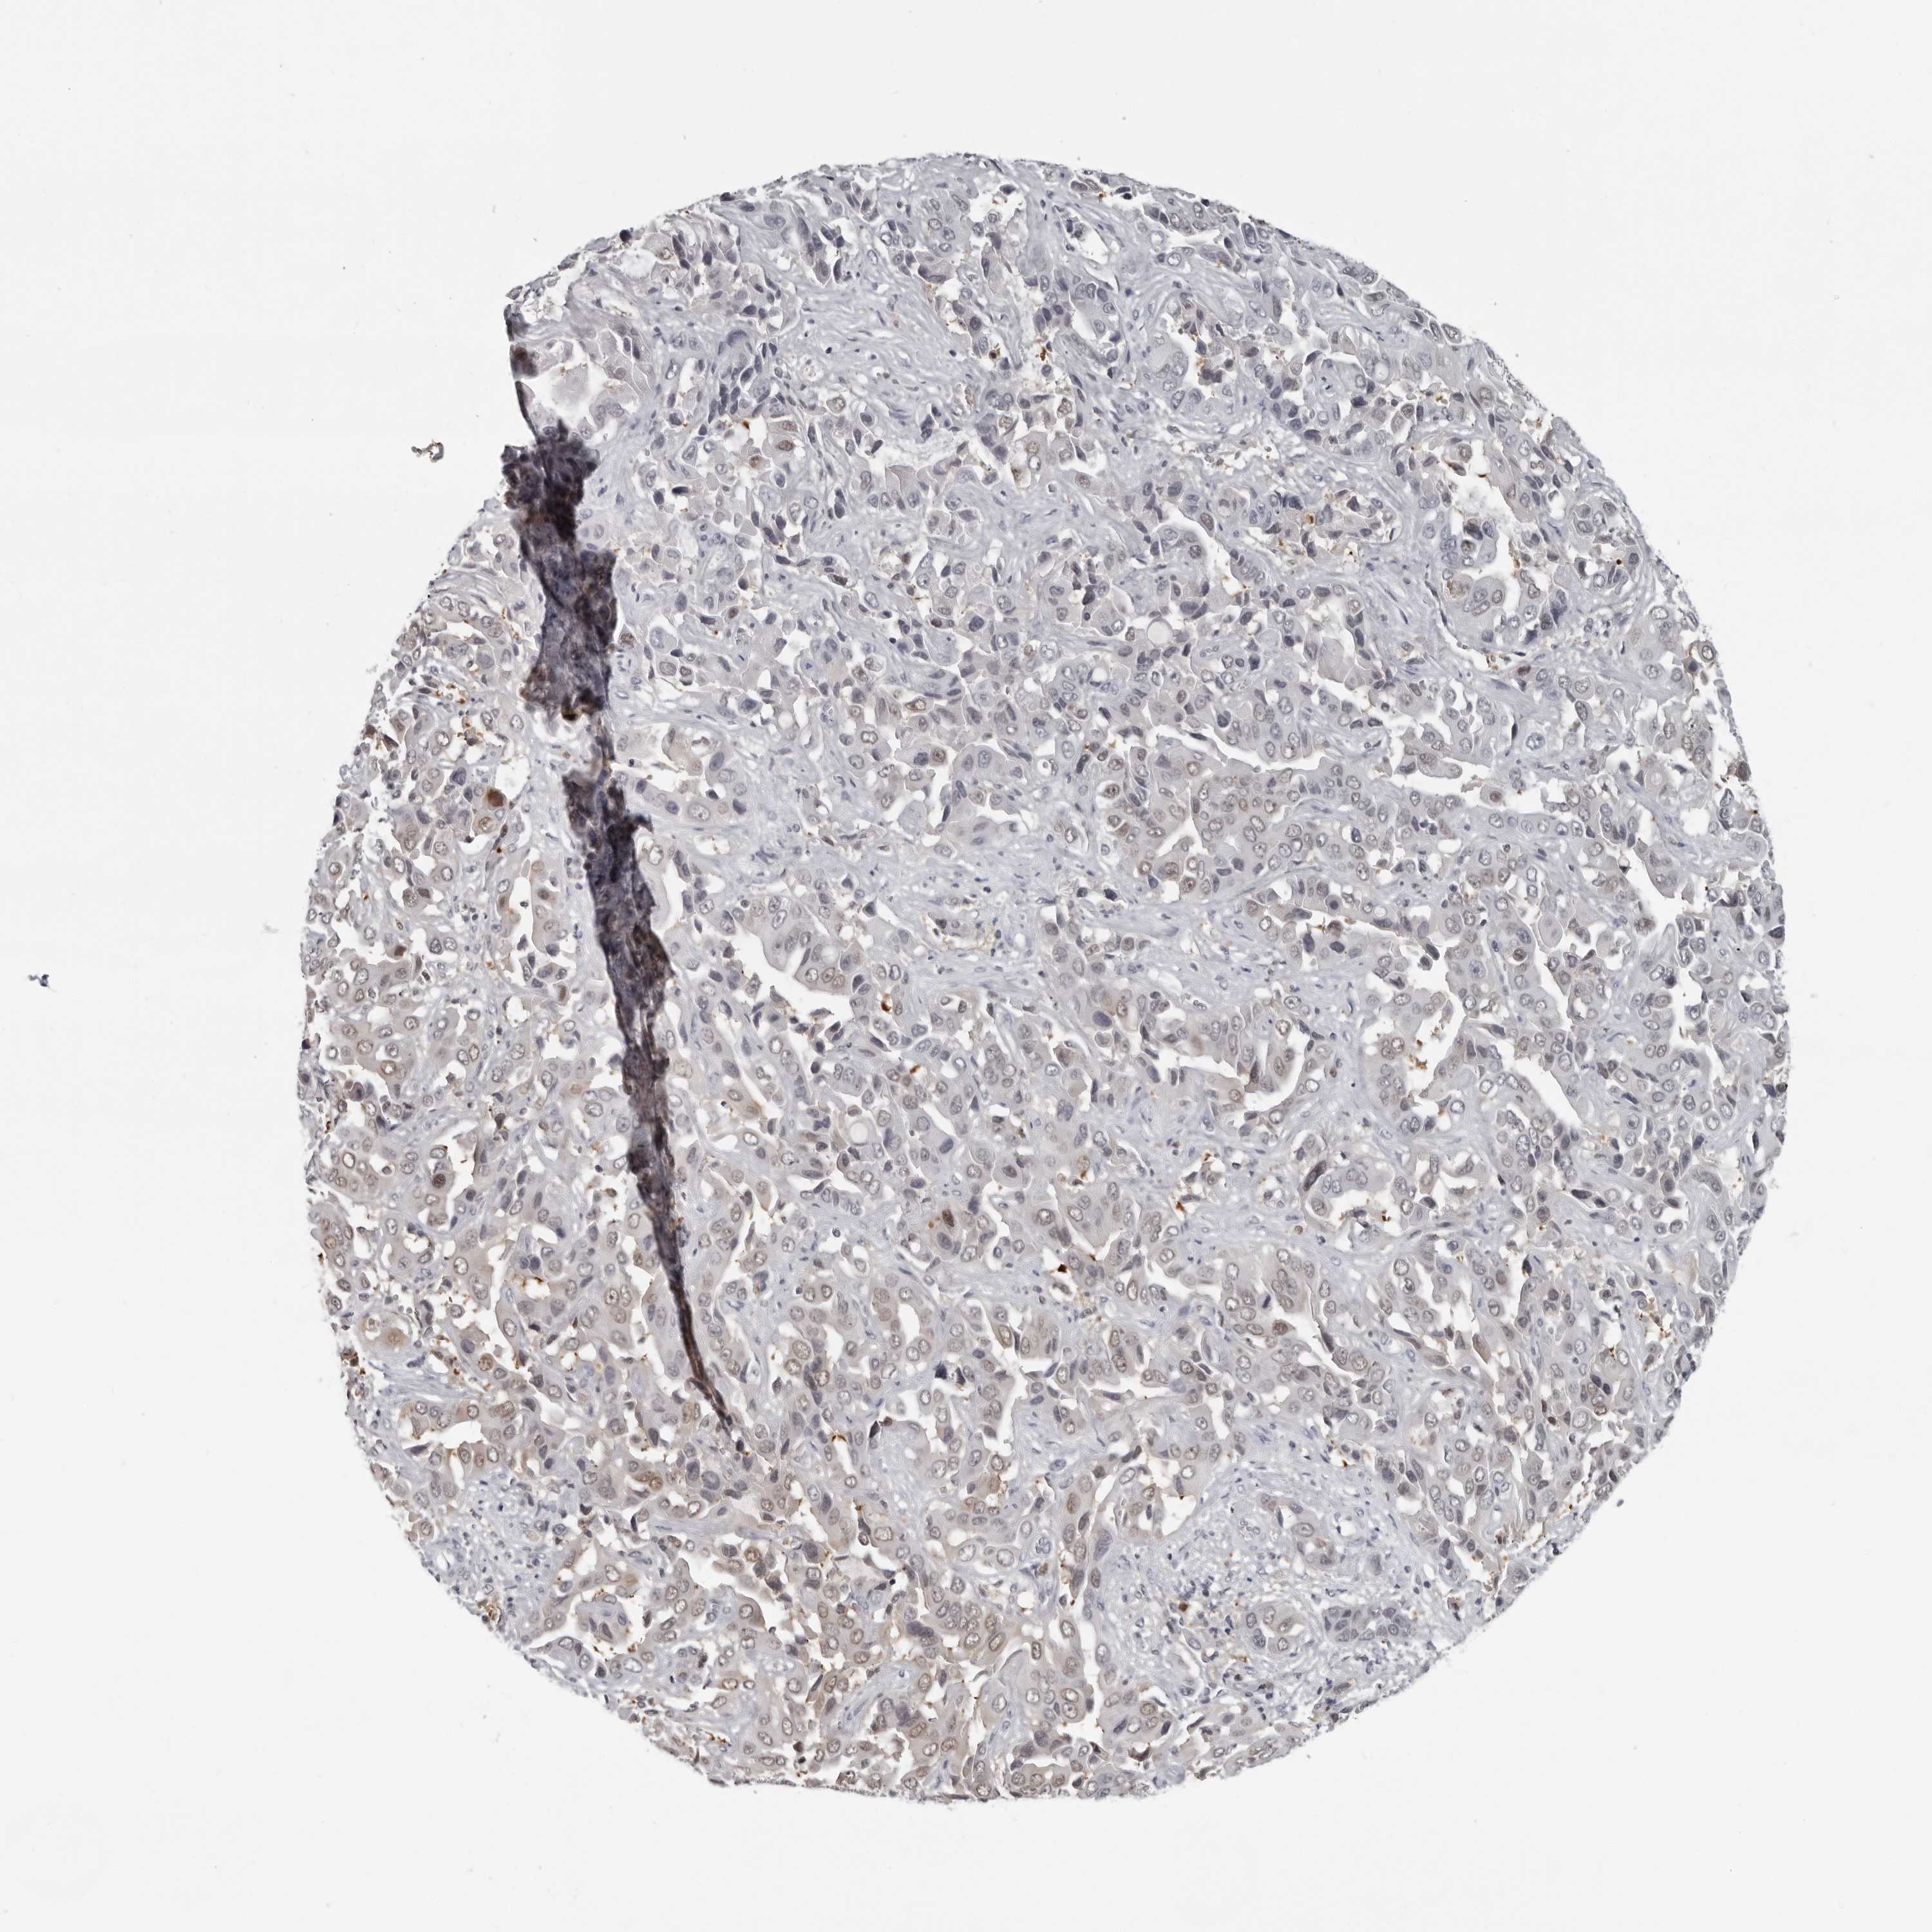

LIVER CANCER - Protein expressioni

A mouse-over function shows sample information and annotation data. Click on an image to view it in a full screen mode. Samples can be filtered based on level of antibody staining by selecting one or several of the following categories: high, medium, low and not detected. The assay and annotation is described here.

Antibody stainingi

Antibody staining in the annotated cell types in the current human tissue is reported as not detected, low, medium, or high, based on conventional immunohistochemistry profiling in selected tissues. This score is based on the combination of the staining intensity and fraction of stained cells.

Each image is clickable and will lead to virtual microscopy that enables deeper exploration of all samples and also displays staining intensity scores, fraction scores and subcellular localization as well as patient and tissue information for each sample.

Antibody HPA028184

Staining

High

Medium

Low

Not detected

Intensity

Strong

Moderate

Weak

Negative

Quantity

>75%

75%-25%

<25%

None

Location

Nuclear

Cytoplasmic/membranous

Cytoplasmic/membranous,nuclear

Cholangiocarcinoma

Carcinoma, Hepatocellular, NOS